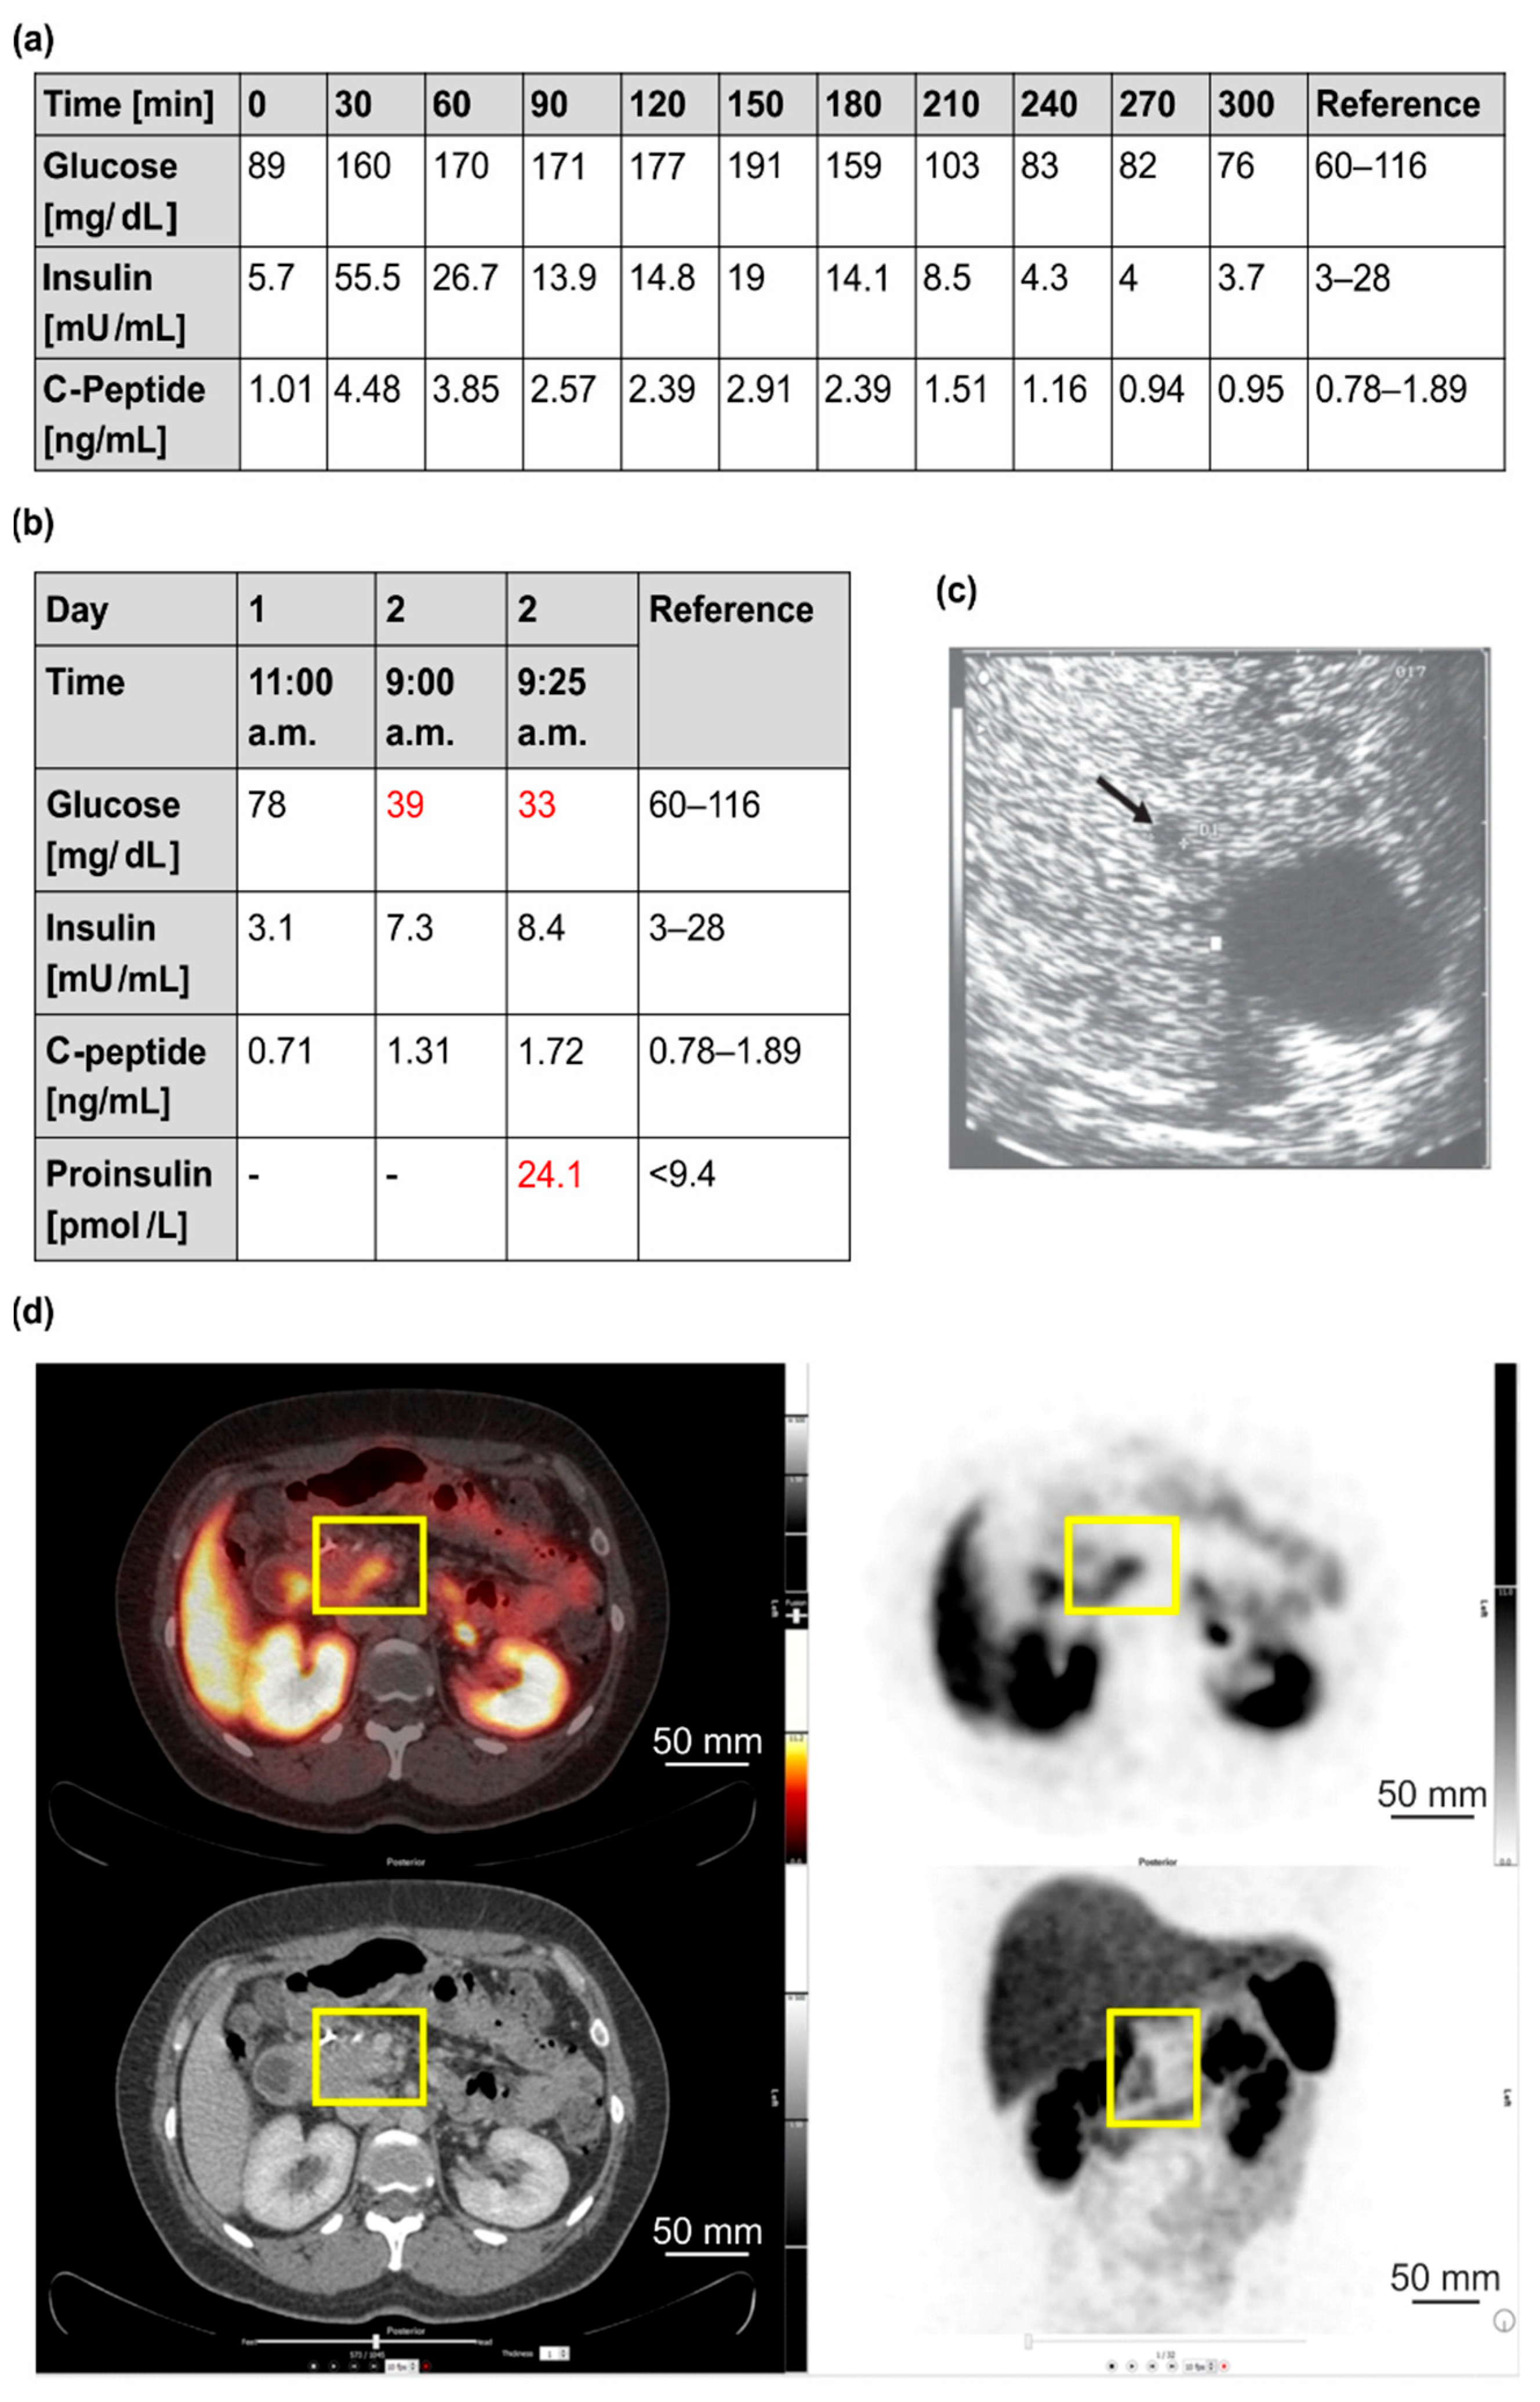

3.1.1. Clinical Case 1; Index Patient (Female, IV4, 48 Years Old at Time of Study)

3.1.2. Clinical Case 2; Sister of Clinical Case 1 (IV3, 57 Years Old at Time of Study)